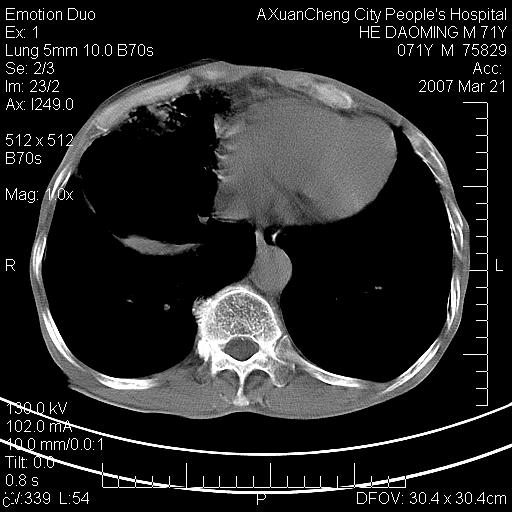

标题: CT7269:[原创] 咳嗽,咳痰,大家讨论右肺病变的部位 [打印本页]

标题: CT7269:[原创] 咳嗽,咳痰,大家讨论右肺病变的部位

1.慢支肺气肿 肺心病 肺大泡;2.叶间裂积液,前胸膜粘连

右侧相当于叶间软组织样密度ct值约50hu,请大家讨论是什么性者病变

右下肺大囊肿伴感染.肺气肿,肺大泡.

考虑:慢性支气管炎合并全小型肺气肿、肺大泡、间质纤维化、感染,右斜裂积液。

考虑慢支,肺气肿,肺大泡,间质纤维化;右侧斜裂液气胸考虑(可能因为肺大泡破裂破入斜裂所致).

考虑病变以右上中肺多发肺大泡为主并感染。请结合临床考虑慢支肺气肿,肺心病。

1双肺慢性支气管炎并全小叶型肺气肿肺大泡2间质性纤维化3右侧斜裂积液

考虑:慢性支气管炎合并右侧全小型肺气肿、肺大泡并感染、双肺间质纤维化,右斜裂积液。

考虑:慢性支气管炎合并右侧全小型肺气肿、肺大泡并感染、双肺间质纤维化,右斜裂积液。右侧斜裂液气胸考虑(可能因为肺大泡破裂破入斜裂所致).